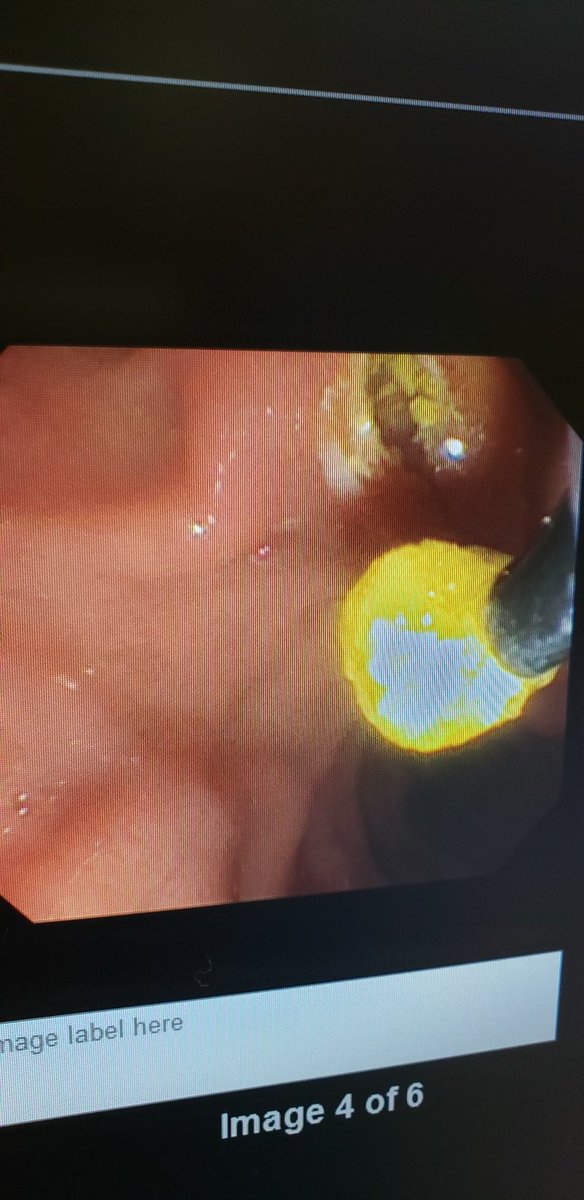

Enhanced Suction During Esophagogastroduodenoscopy: Official journal of the American College of Gastroenterology | ACG @AmCollegeGastro Congratulations @ZSobaniMD and @swathipaleti for putting this idea into video @AmJGastro #ThinkingOutsideTheBox #endoscopy #innovation